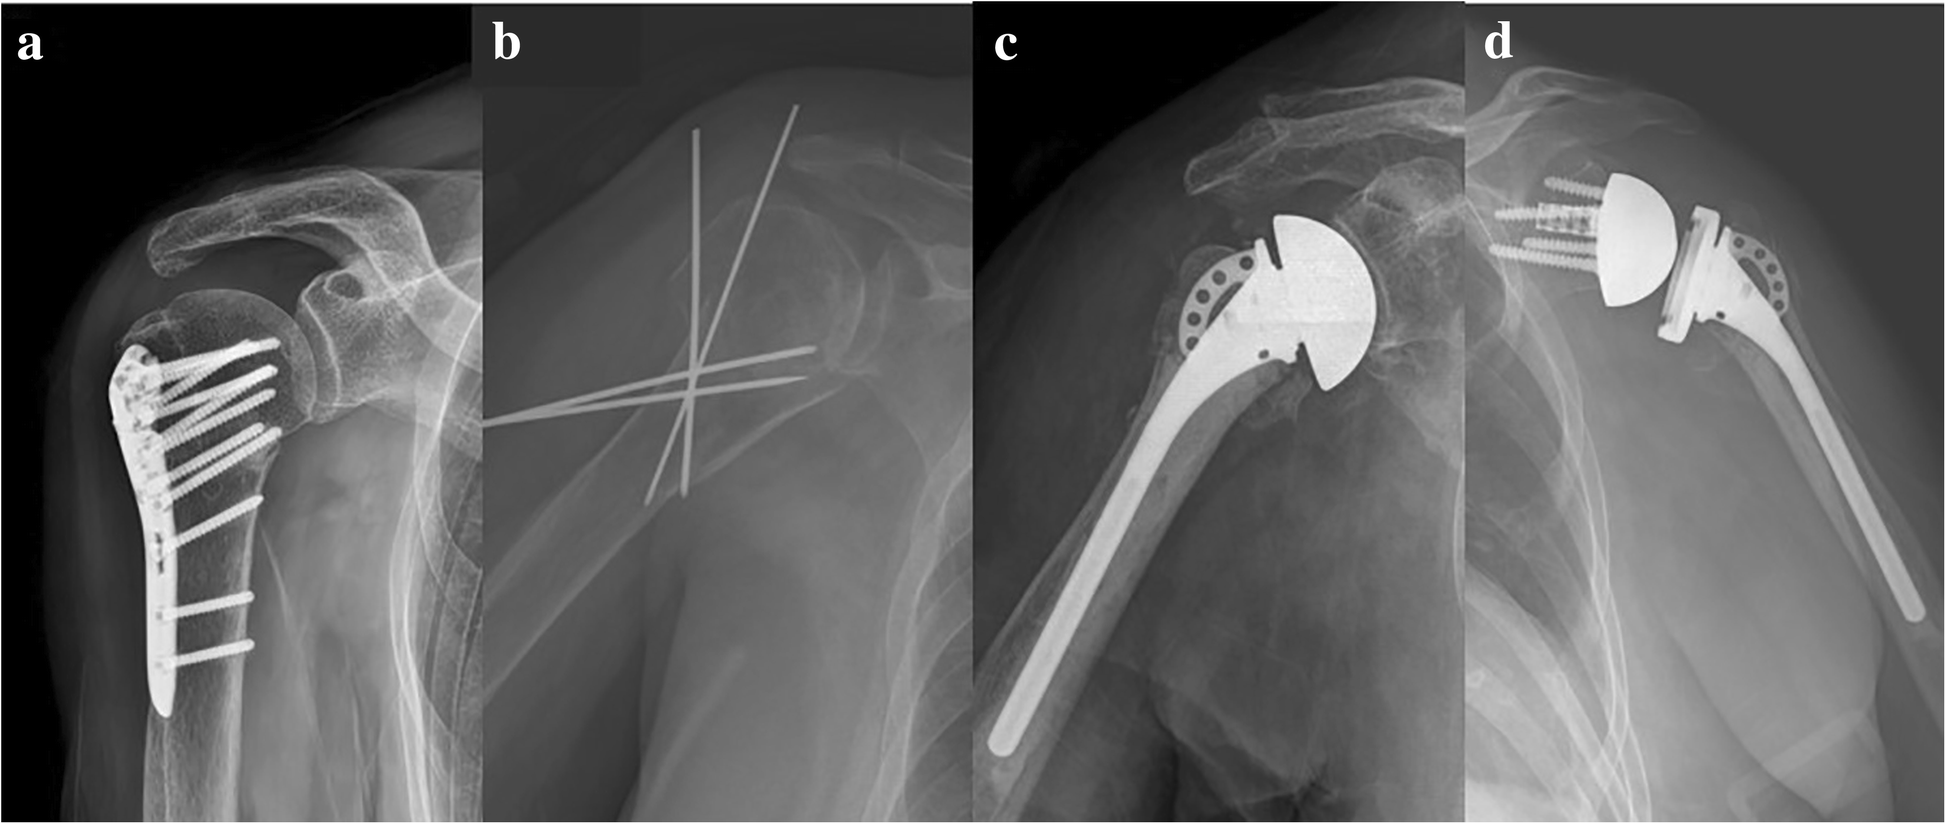

Proximal humerus fracture treatment varies by surgeon preference and patient factors. Orif surgery for a proximal humerus fracture is a treatment option for displaced shoulder fractures. She subsequently undergoes surgery to treat the fracture, with immediate postoperative radiographs shown in figure a.

During this procedure, an incision will be made and a metal plate will be attached to the humerus to hold the bone in place while it heals. The combination of age, potential osteoporosis or weakened bones, and. A dose of antibiotics given prior to surgery helps to make this risk as small as possible.

Between 1999 and 2018, 425 proximal humerus fractures underwent acute surgical management: In most cases, a proximal humerus fracture will not require surgery. However, many complications still occur